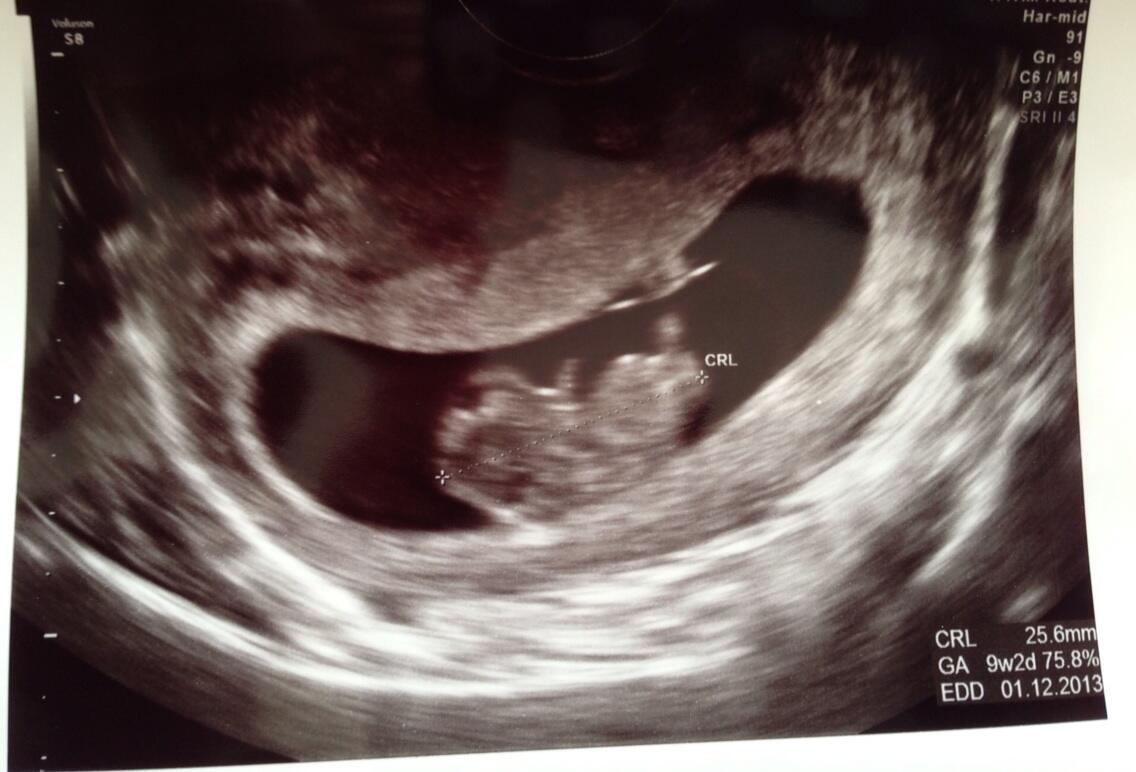

It didn't start well as I got a ticking off from the sonographer as my bladder was not full enough. As many of you know there is a delicate balance between having a full bladder and being so desperate for a pee you can hardly walk into the room. On this occasion I got it wrong! Also, apparently my uterus was tilting backwards which made it doubly difficult to get a good look at what was going on inside. We swapped to an internal scan which gave us a much clearer picture.

One baby shaped baby, measuring bang on his/her dates of 9 weeks 2 days and one lovely heartbeat.